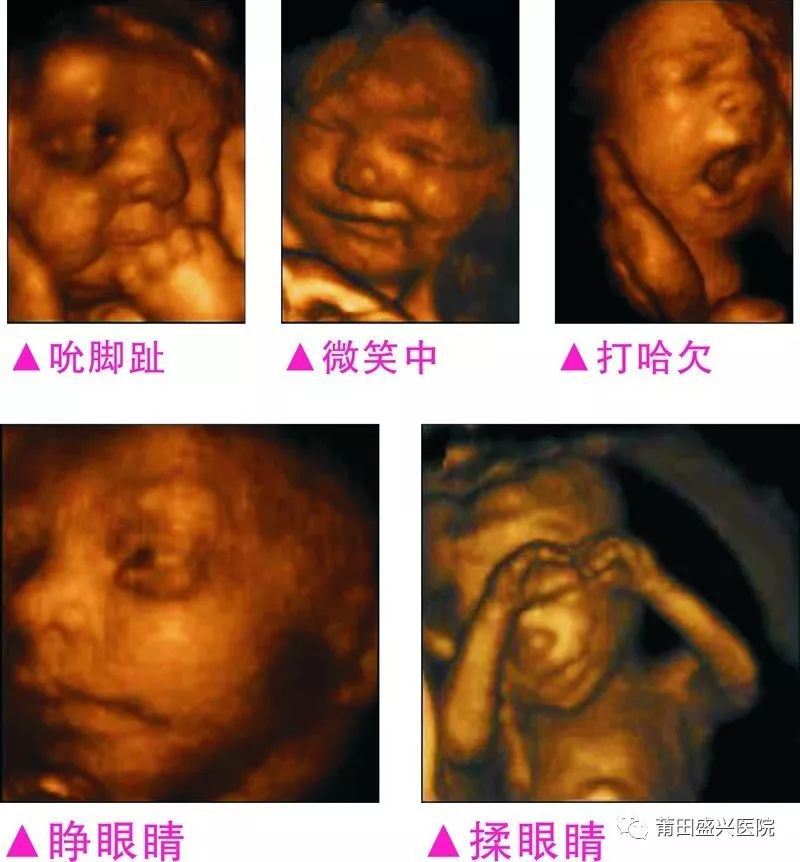

您一定不知道寶寶有多調(diào)皮可愛(ài)

你一定不知道寶寶這么小就有這么多表情

四維容積成像技術(shù),智能光源系統(tǒng)展現(xiàn)梯度亮度,渲染畫面,提高容積成像品質(zhì),高清顯示腹中寶寶的實(shí)時(shí)動(dòng)態(tài)影像,完整記錄寶寶的一舉一動(dòng),讓準(zhǔn)爸媽與寶寶Di一次幸福“見(jiàn)面”,更可刻錄成高清視頻,送給未來(lái)寶寶的珍貴禮物。